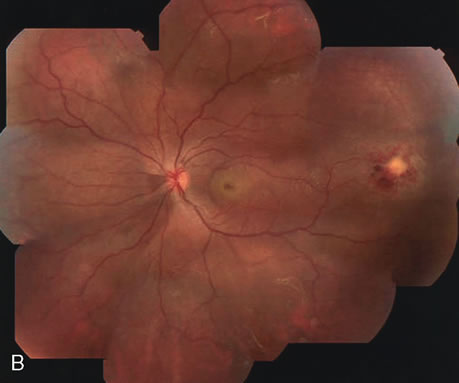

Clinically discernible peripheral dependent bullous neurosensory detachments have been described in patients with chronic CSC.85–92 Yannuzzi and co-workers first characterized the presence of RPE atrophic tracts extending inferiorly in the fundus periphery secondary to antecedent retinal detachment in patients with CSC.85 Presumably, there is a particularly severe and/or longstanding leakage of fluid from an RPE defect in the subretinal space at the posterior pole. The subretinal fluid gravitates inferiorly to form a dependent neurosensory detachment in a “flask,” “teardrop,” “dumbbell,” or “hourglass” pattern (Fig. 31). Sometimes the tract of subretinal fluid connecting the macular detachment with the bullous neurosensory detachment in the inferior hemisphere is so shallow that it is very difficult to appreciate. The RPE under the chronic retinal detachment experiences atrophic changes that appear as atrophic RPE tracts connecting the posterior pole with the dependent retinal detachment. The retina itself develops secondary manifestations including pigment migration, capillary dilatation (telangiectasia) proximally and capillary nonperfusion (ischemia) distally to the area of detached retina (see Fig. 31). The changes in the RPE consist of both RPE atrophy and pigment clumping in the form of perivascular deposits or bone spicules, a condition described by Gass as a “pseudoretinitis pigmentosa–like atypical CSC presentation.”87

Fig. 31. A 47-year-old woman with an18-year history of central serous chorioretinopathy in both eyes. A. Color photograph composite of the left eye shows bullous dependant detachment of the neurosensory retina inferiorly. B. Fluorescein angiogram composite reveals diffuse decompensation of the retinal pigment epithelium, multiple scattered pigment epithelium detachments 9PEDs), and obliteration of the retinal capillaries in the region of the detachments. Note the presence of early neovascularization at the junction between perfused and non-perfused retina. C. Clinical photograph of the left eye shows PED superior to the optic disc partially surrounded by fibrin deposits. D. Fluorescein angiography confirms the presence of active leakage from the serous PED. E, Color photograph composite of the same eye 2 months after laser treatment of the site of leakage reveals partial resolution of the detachment and lipid precipitation. F. Clinical photograph composite 16 months after the laser treatment in the area of the leakage shows complete resolution of the detachment and partial reperfusion of the inferior retina.